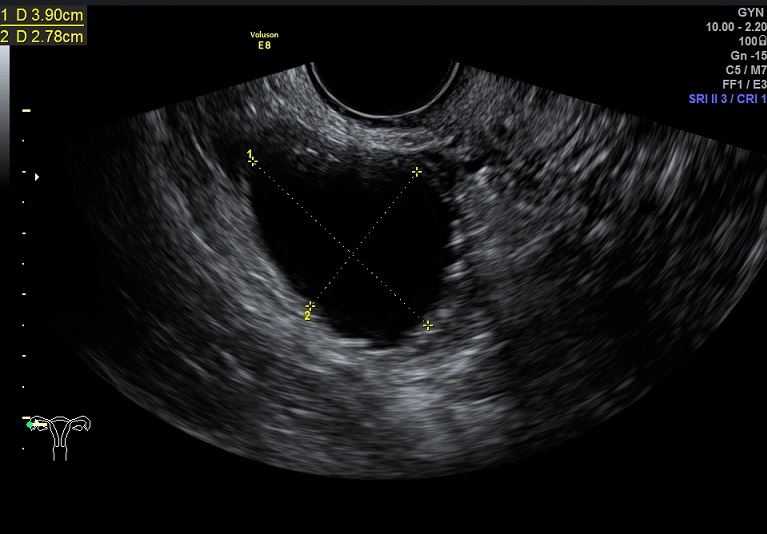

左卵巢黄体 右卵巢囊性结构